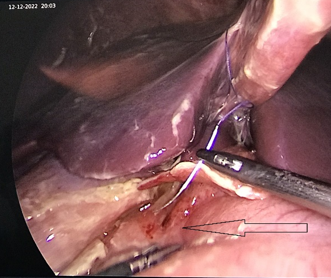

Lỗ thủng dạ dày phát hiện trong khi mổ nội soi

quá trình phẫu thuật nội soi quan sát thấy ổ bụng chứa nhiều dịch mủ bẩn, dịch

tiêu hóa, phát hiện 1 lỗ thủng mặt trước dạ dày, ngay sát gan ( tiền môn vị ).

Mặc dù vị trí khó khăn, nhưng bằng kinh nghiệm và tay nghề cúa bác sỹ phẫu thuật,

BN đã được khâu lỗ thủng, lấy dịch bẩn, làm sạch ổ bụng.